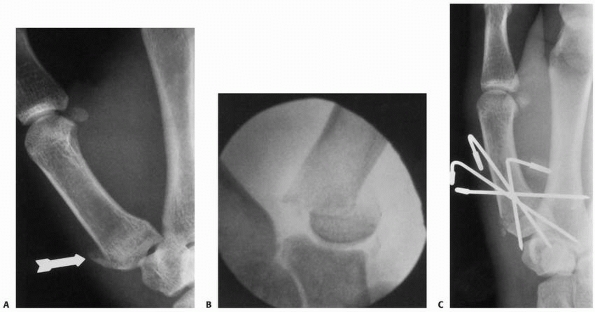

![]() |

FIGURE 8-36 A,B. A 16-year-old male sustained a dorsal S-H IV fracture of the middle phalanx. C,D.